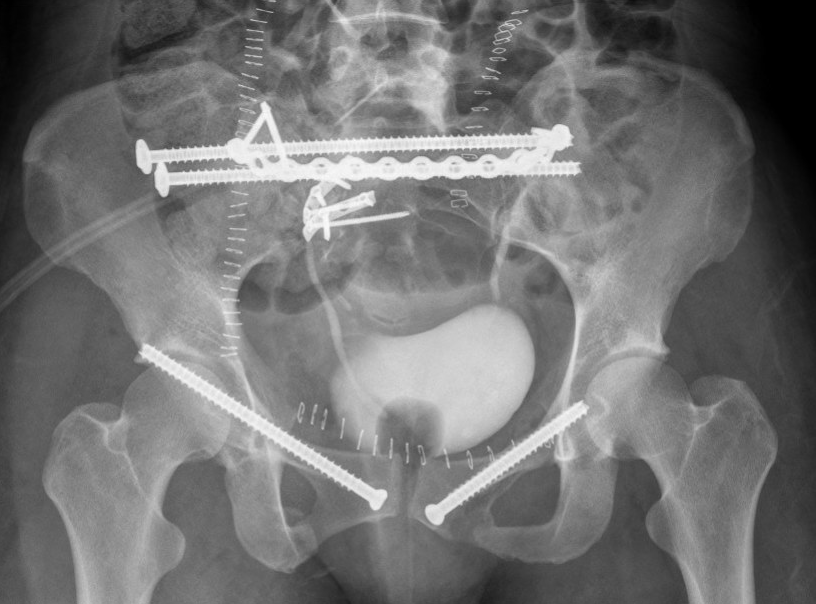

Definitive Management

Lumbosacral fixation with SI screw - triangular osteosynthesis

Sacral plate, sacroiliac screws, ramus screws

Posterior stabilisation critical

Options

- sacro-iliac screws

- trans-sacral trans-iliac screws

- trans-iliac posterior tension band plating

- lumbosacral fixation

Anterior stabilisation

Pubic symphysis plates

Percutaneous ramus screws